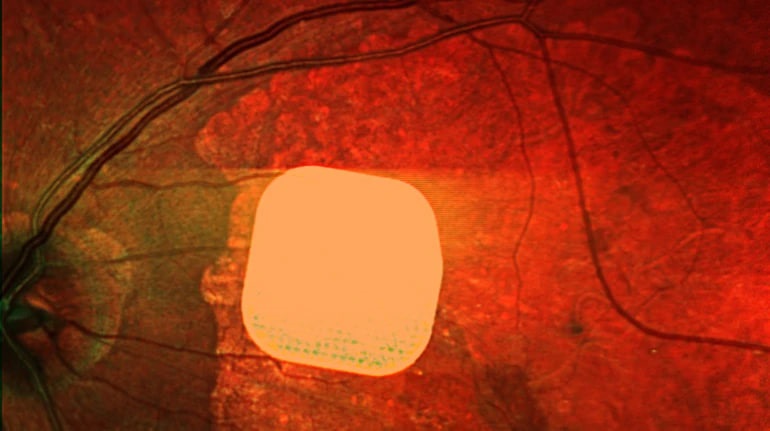

Британські лікарі успішно випробували новий електронний імплант Prima, який допомагає відновити зір пацієнтам із макулодистрофією, що є однією з головних причин втрати зору у людей після 50 років. Цей мікрочип розміром всього 2×2 міліметри встановлюють під сітківку ока пацієнта. Під час операції пацієнту також під’єднують систему окулярів доповненої реальності з камерою і мінікомп’ютером. Камера зчитує зображення, перетворює його і передає на мікрочип, який активує клітини сітківки, а потім сигнал надходить до мозку, утворюючи візуальне сприйняття. У дослідженні взяли участь 38 пацієнтів із віковою макулодистрофією, і після імплантації 84% з них знову змогли розрізняти літери, цифри та слова. Ця технологія може значно поліпшити якість життя людей з важкими зоровими порушеннями, допомагаючи їм повернути частково зір.